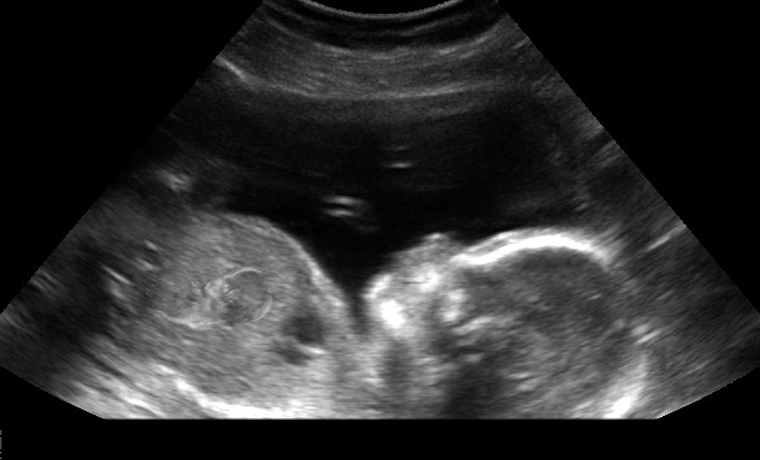

หญิงครรภ์ 8 เดือน คนนี้มีชื่อว่า Mary Lambert ได้เดินทางไปโรงพยาบาล Silverstein Memorial ใน Portland เพราะคิดว่าตนเองกำลังจะคลอดลูก เมื่อแพทย์ตรวจเบื้องต้นกลับไม่สามารถระบุสาเหตุที่มีอาการปวดท้องอย่างรุนแรงนี้ได้ จึงทำการอัลตราซาวด์ทารกในครรภ์จึงได้พบกับความจริงที่ต้องตกตะลึงว่าทารกในครรภ์ของเธอนั้นกำลังตั้งครรภ์เช่นกัน

นายแพทย์ Joseph Goldsmith กุมารศัลยศาสตร์ กล่าวว่าเขาไม่เคยพบเคสแบบนี้มาก่อนเลยในชีวิต และไม่คิดว่าเหตุการณ์แบบนี้จะเกิดขึ้นกับใครได้ เพราะนี่ก็เป็นครั้งแรกที่พบว่าทารกในครรภ์ต้องกลายมาเป็นผู้ตั้งครรภ์ด้วย เคสแบบนี้หายากมากและไม่คิดว่าจะเกิดขึ้นกับใครด้วย

แพทย์ของ Lambert กล่าวว่า ไม่น่าเชื่อเป็นอย่างมากด้วยที่เด็กทั้ง 2 คนนั้นดูมีสุขภาพดีเป็นอย่างมาก เมื่อ Lambert คลอดลูกในเดือนหน้า ทารกก็จะมีครรภ์อายุ 6 เดือน ซึ่งในทารกแรกคลอดรายนี้เราจะต้องดูแลชีวิตในโรงพยาบาลอย่างดีที่สุดเพื่อให้แพทย์ได้เข้าถึงได้ดีที่สุดทุกสภาพการณ์